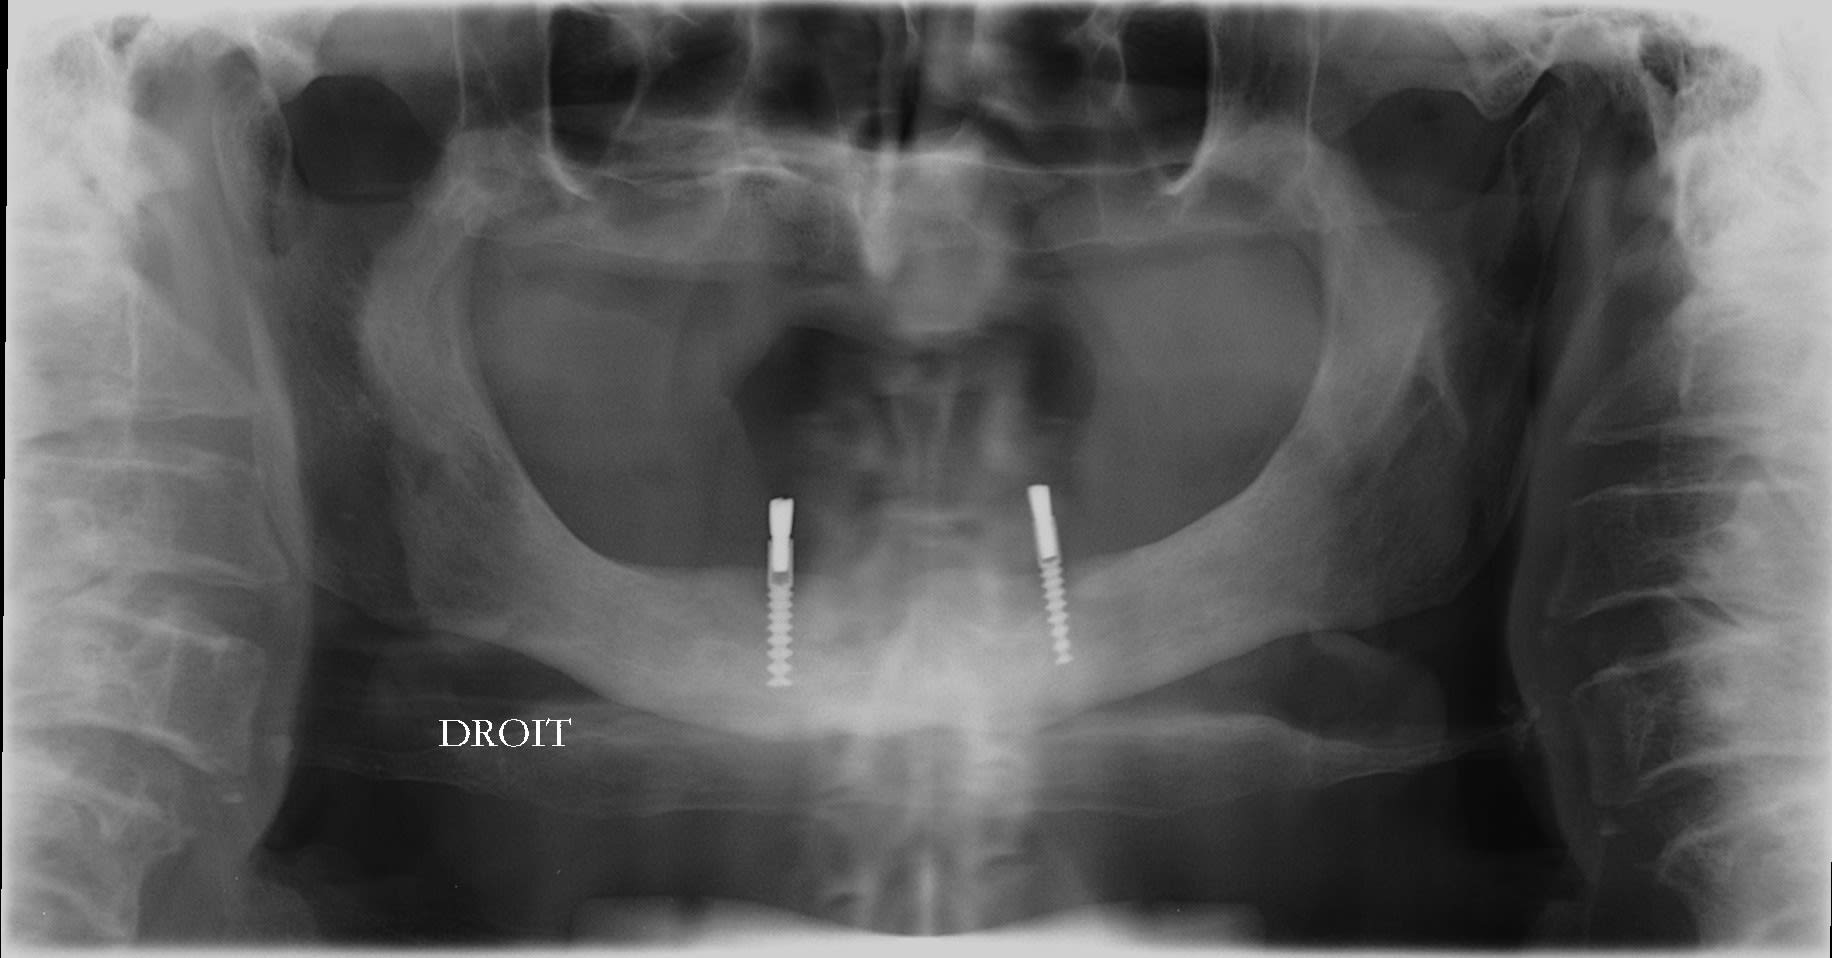

De la pano la moins marrante Ă  la plus marrante :

Regarde moi ça 4 Implants et on va jusqu'aux 7 voir jusqu'aux 8 sans problùme 😊